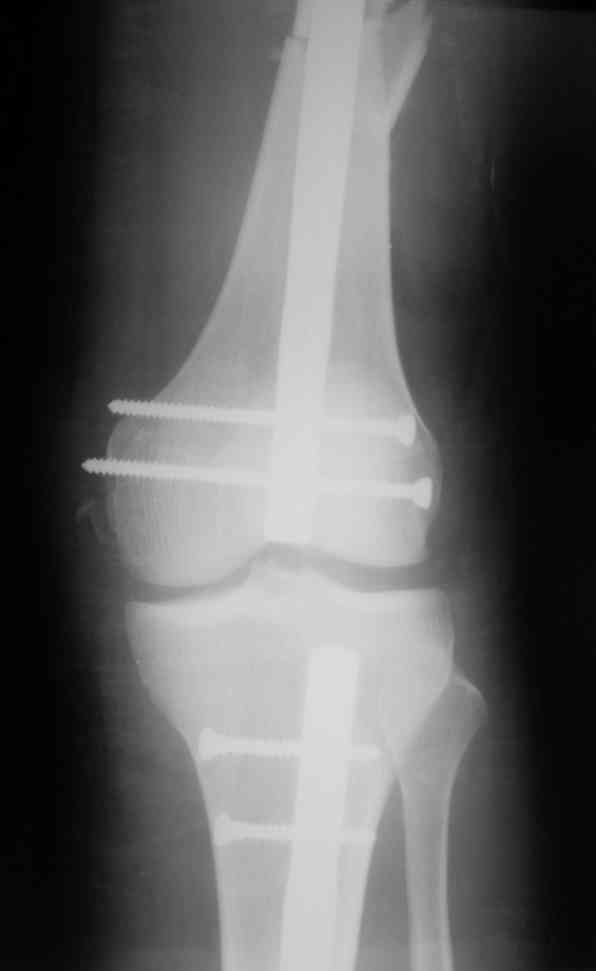

Вчера первый раз синтезировали голень гвоздем Fixion.

Спиральный оскольчатый перелом, ниже середины, у молодого парня. Сделали "классический" вариант гвоздя, который еще без винтов. Получилось все легко. Не торопясь, сделали операцию минут за 20. См. фото.

В отношении ранней нагрузки при спиральных переломах лучше не торопиться. По данному случаю необходимо достигнуть исчезновения щели между штифтом и внутреним кортексом по Rg. А так картинка прекрасная - и длина сегмента и репозиция. Можно поздравить, коллега!